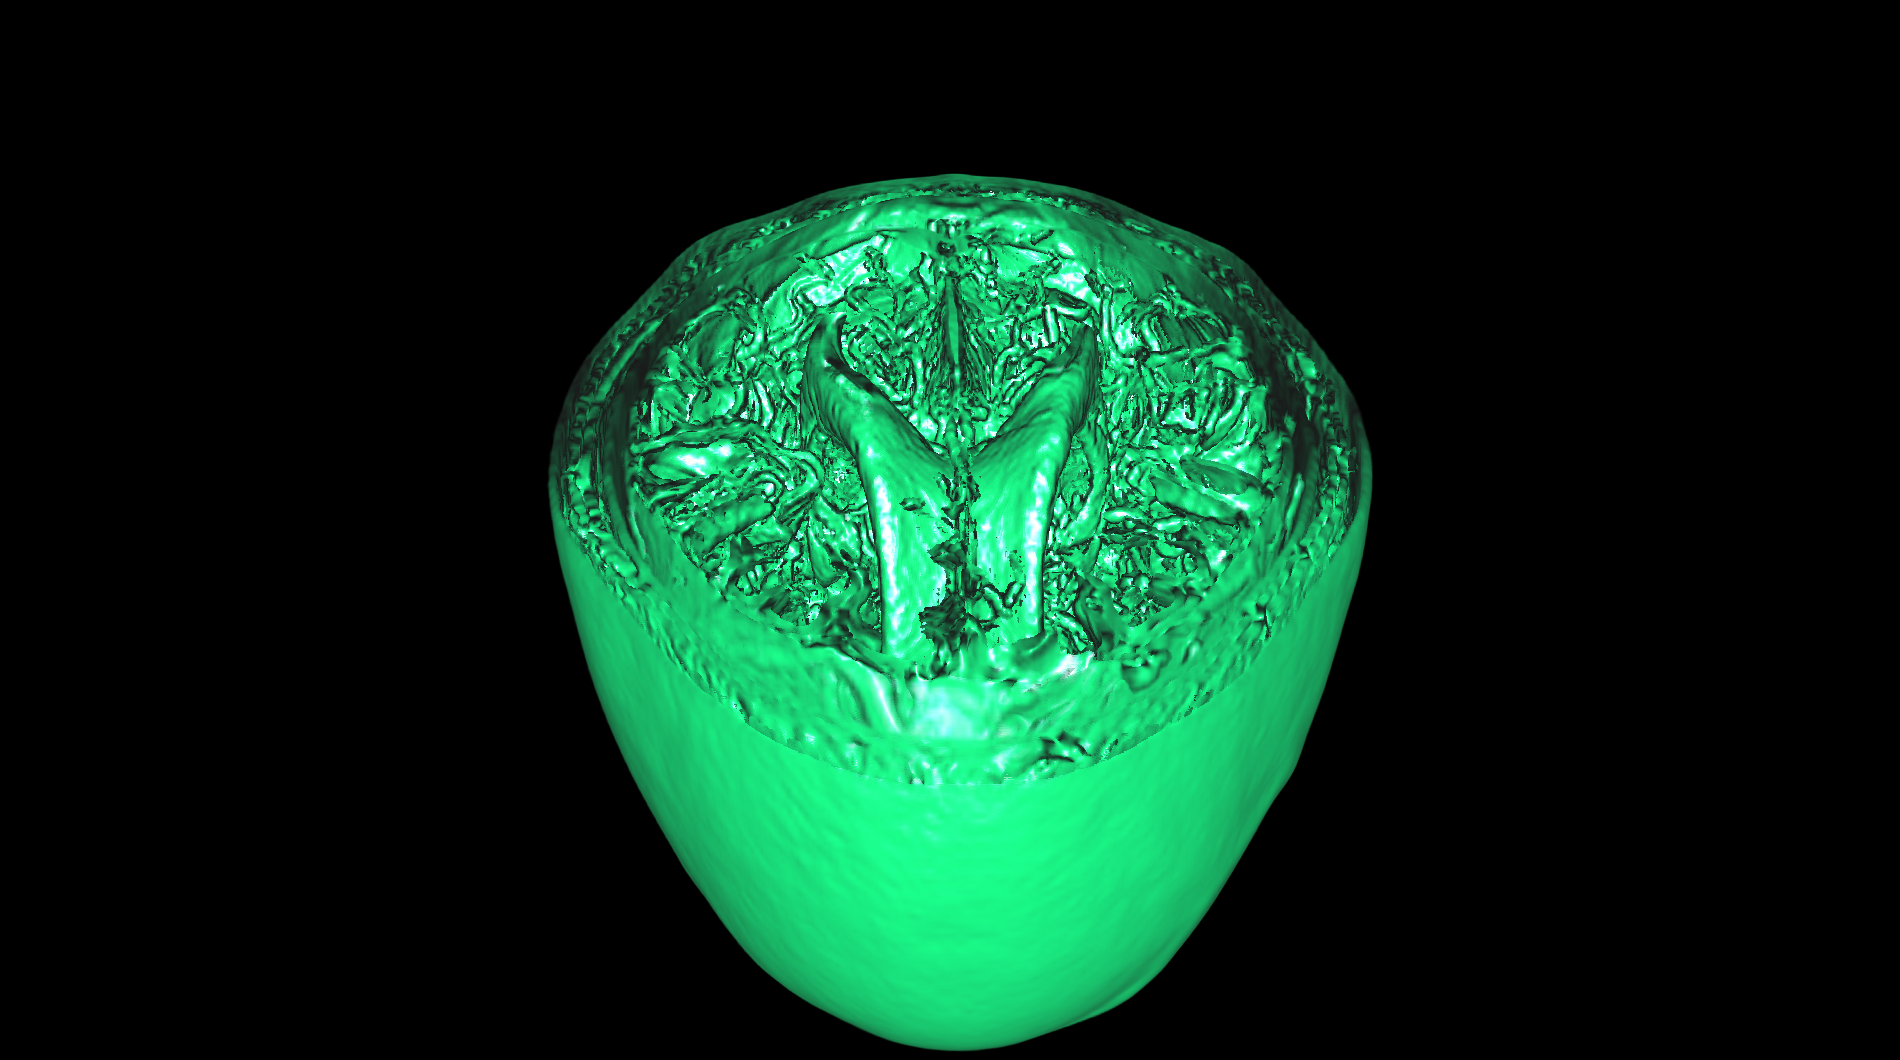

medical-03

The medical-03 viewset demonstrates the performance of several medical visualization volume rendering techniques. The first is "slice rendering", where many 2D slices are projected through the volume and composited on the screen. The second is "raycasting" where rays are projected through the volume accumulating the final pixel color. Two different transfer functions are used: 1D, where the density is used to look up each voxel color, and 2D, where density and gradient magnitude are used to look up each voxel color. A clipping plane is used in several tests. The Tuvok visualization library is used for rendering.

medical-03 composite score: 25.67

The composite score is a weighted geometric mean of the subtest scores. See the table below for subtest weights and FPS scores for this run.

Subtest results

Click on each thumbnail image below to display the subtest's screen grab.

The results table above includes the details about each test within a viewset. Viewsets are often comprised of many tests which produce a frame rate. Frame rate is computed as the average Frames Per Second (FPS), or the total number of frames rendered divided by the time in seconds to render those frames. These FPS values are then used to compute the composite score using the weights for each test.